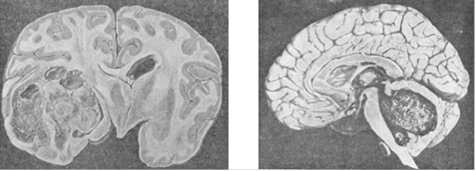

Астроцитома височной доли мозга; и медуллобластома червя мозжечка и IVжелудочка.